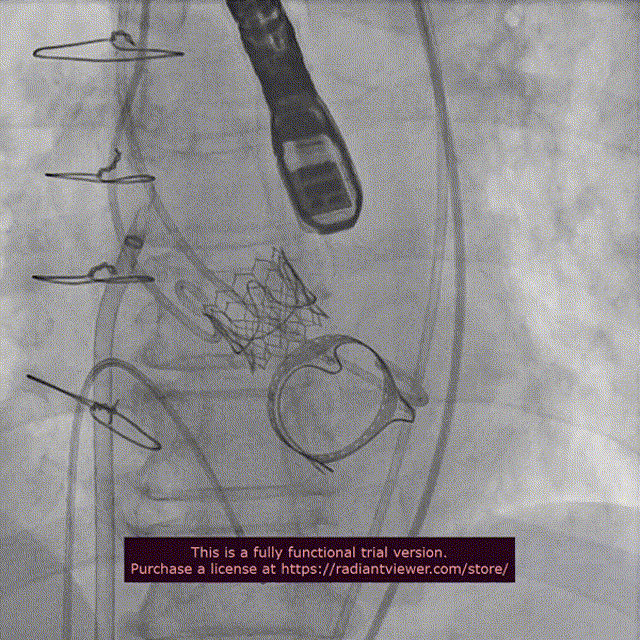

近日,中国医学科学院阜外医院潘湘斌教授团队,在多科室的通力配合下,凭借扎实的手术功底顺利完成一例经导管主动脉瓣和二尖瓣瓣中瓣置换术。

手术过程